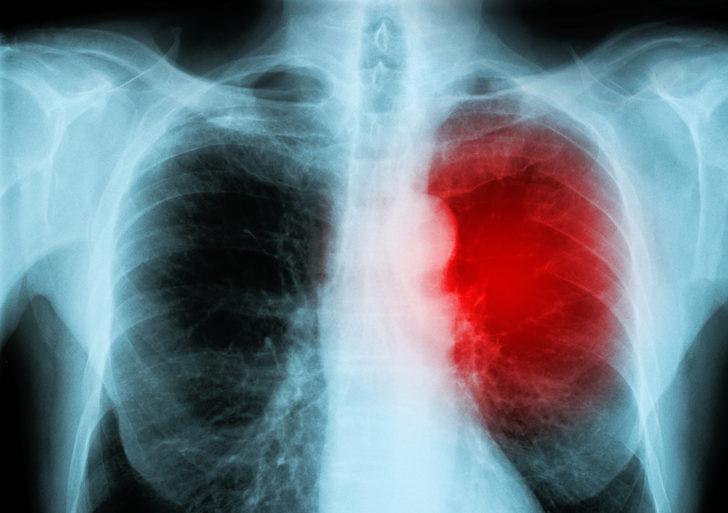

Beylikdüzü'nde geçen hafta hayatını kaybeden 2 ve 5 yaşlarındaki iki çocuğun ölümüyle ilgili inceleme sürüyor. Üst solunum yolu enfeksiyonu bulgusuyla tedavi altında olan çocukların ani ölümlerine, kalp kası iltihabı olarak bilinen ‘miyokardit’in neden olduğu düşünülüyor. İstanbul İl Sağlık Müdürlüğü çocuklardan birinde miyokardit belirlendiğini, ancak incelemelerin devam ettiğini açıkladı.

Konuyla ilgili uyarılarda bulunan Acıbadem Üniversitesi Tıp Fakültesi’nden Çocuk Kardiyoloji Uzmanı Prof. Dr. Ender Ödemiş, "Grip virüsü kalp kasına yerleşerek kalp kası iltihabına neden olup ‘miyokardit’e yol açabilir. Çoğu çocuk hiçbir belirti göstermeden hastalığı atlatırken, bazı çocuklarda kalp nakline, hatta ölüme varan ciddi sonuçlar yaşanabilir. Her grip kalbi vuracak diye bir şey yok, ama çocukta ateş olmadığı halde taşikardi dediğimiz nabız yüksekliği varsa, kalp açısından da değerlendirilmeli" dedi.

"Miyokardit, yani kalp kasının iltihabı, aslında tahminimizden daha fazla özellikle çocuklarda görülen bir sağlık problemi. Gribe yol açan influenza virüsü nedeniyle görülebildiği gibi, viral üst solunum yolu enfeksiyonu yapan diğer bazı virüslerden sonra da kalp kasının iltihaplanması mümkün. Bu türden miyokardit’lerin teşhisi gerçekten çok kolay değil. Belirtiler üst solunum yolu enfeksiyonu veya grip ile aynı çünkü. Ancak çok önemli belirleyici bir durum, taşikardi dediğimiz kalbin normalden çok hızlı atması durumu var. Miyokardit olan çocuklarda bu, daha belirgin olur. Üst solunum yolu enfeksiyonu olan çocuklarda ateşle birlikte taşikardi görülebilir. Ama miyokardit’te ateş çok yükselmeden de kalbin çok hızlı attığı fark edilebilir. Yani ateşle orantısız bir şekilde kalbin çok hızlı attığı fark edilirse mutlaka çocuğun bir kalp doktoru tarafından da değerlendirilmesi gerekir."